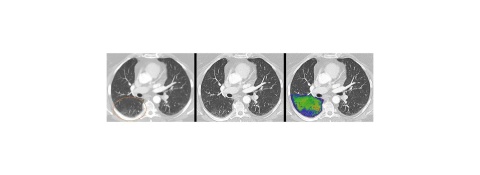

Mit einem neuartigen Systemkonzept und neuer Detektortechnologie läutet dieses System eine neue Ära in der Computertomographie ein, einer Technologie, die die Richtung vieler medizinischer Entscheidungen beeinflusst. Dank der Bilder quantenzählender CTs profitieren weltweit mehr Menschen von präzisen und umfassenderen Untersuchungen bei niedriger Strahlen- und Kontrastmitteldosis – von onkologischen Verfahren über Herzdiagnostik bis hin zu Verlaufskontrollen der Lunge bei Atemwegserkrankungen.